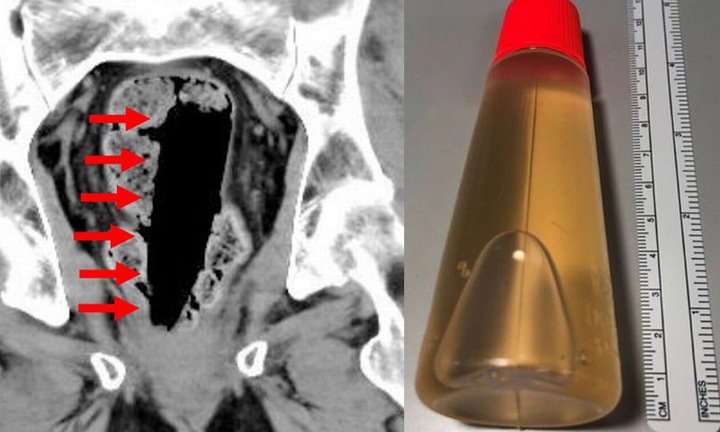

Người vợ sợ run khi phát hiện chồng mình bất tỉnh trong bồn tắm sau khi ông cố gắng chữa chứng táo bón bằng cách nhét nguyên một lọ keo hình trụ vào trực tràng.